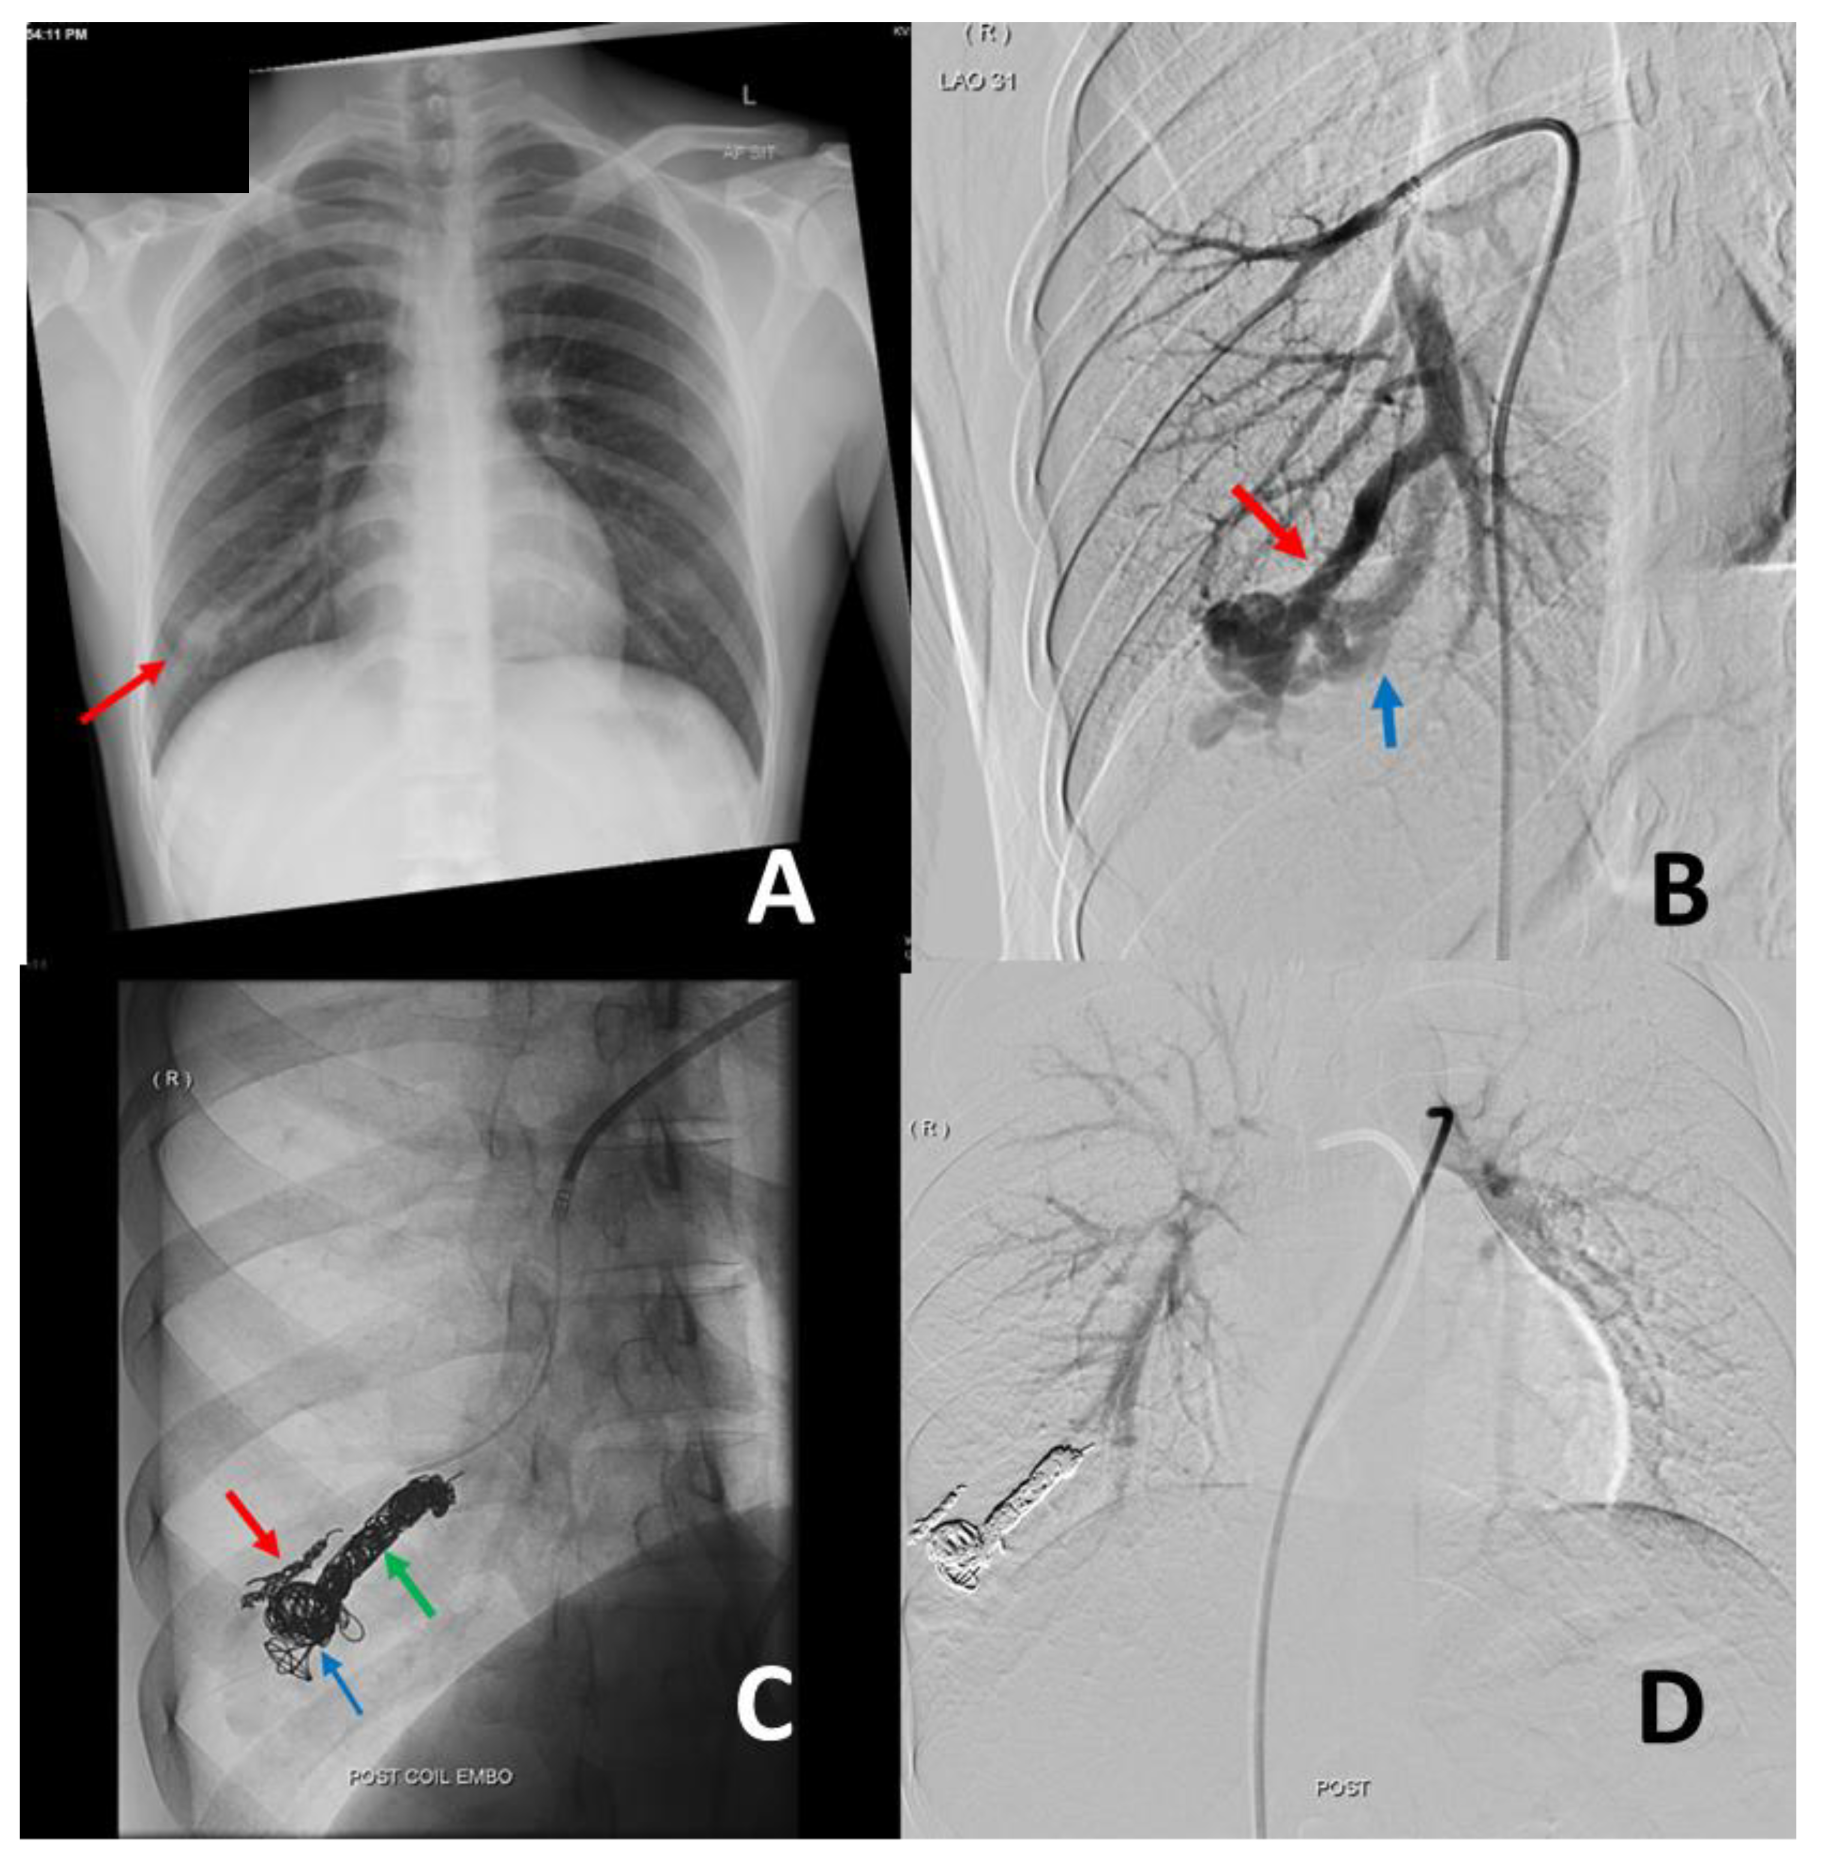

3. Management of PAVM